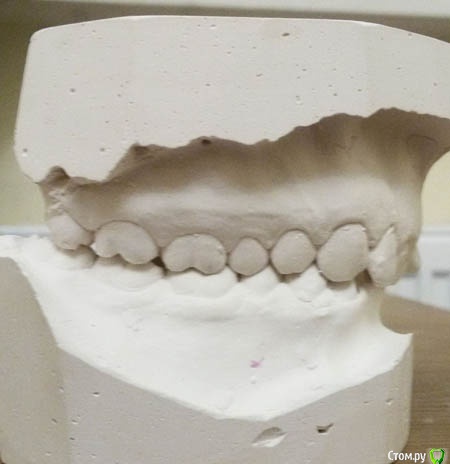

Беспокоит: Возраст 30 лет.  с 15 лет щелчки в суставе, полгода назад появилась периодическая боль - в области сустава, напряжение в жевательных мышцах, в шее  (с шеей вообще давние проблемы - не знаю, что первопричина болей), боли в затылке, голове. Глубокий прикус. Решил прикус исправлять в надежде, что боли уменьшатся.  На снимках видно, что челюсть нижняя заблокирована в заднем положении, мешают верхние резцы, головка сустава смещена

Часть из этого прикрепляю сюда. Ниже - заключение МРТ

Частичное переднее смещение суставного диска ВНЧС справа в положении с закрытым ртом, полная репозиция диска в положении с открытым ртом. Частичное переднее смещение наружного отдела суставного диска ВНЧС слева в положении с закрытым ртом (за счёт внутренней ротации диска), полная репозиция диска в положении с открытым ртом. Остеоартроз ВНЧС справа 1 ст.